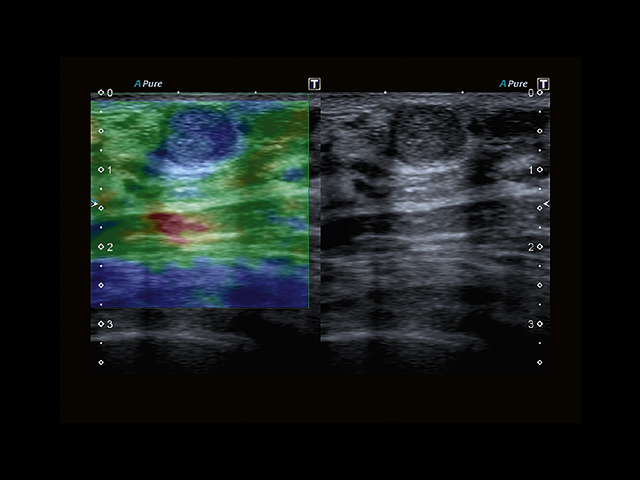

Обновленная версия легендарного УЗ-сканера. Стационарный аппарат экспертного класса Aplio 500 Toshiba NEW, визуализирует анатомические структуры в высоком разрешении. Модель позволяет выявить микрокальцификаты, новообразования, нарушения в работе сердца, сосудов и мышц. Присутствует функция виртуальной эндоскопии, 4D-сканирования, эластометрии тканей, УЗИ с контрастированием. За повышение качества изображения отвечают технологии ApliPure и Superb Microvascular Imaging. Первая задействует возможности пространственного и частотного кодирования, формирует цельный визуальный ряд с сохранением клинических маркеров. Вторая улучшает отображение микрососудистого русла, используя доплеровский эффект. Модель оснащена 21-дюймовым монитором, имеет 4 активных порта. Возможно подключение педиатрических, интраоперационных, лапароскопических и чреспищеводных датчиков.

• MicroPure. Высокотехнологичное решение в области выявления микрокальцификатов – маркеров новообразований злокачественного типа. Маркеры идентифицируются путем изучения затененных изображений целевого участка. Микрокальцификаты отображаются в виде белых пятен.

• SMI. Опция, упрощающая визуализацию микроциркуляторного русла. С ее помощью обследуются сосуды с низкой интенсивностью кровотока, изучаются наиболее тонкие структуры. SMI упрощает диагностику новообразований, минимизирует вероятность ошибки.